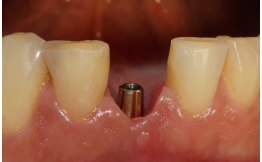

Após os três meses, foi realizada a abertura do implante e foi instalado um cicatrizador, que permaneceu no local por dez minutos para manter os tecidos afastados.

Após esse período, foi selecionado o pilar, e um Pilar Ideale reto de 3.3 X 4.0 X 1.5 mm foi instalado e torqueado a 20 Ncm (Figuras 13 e 14).